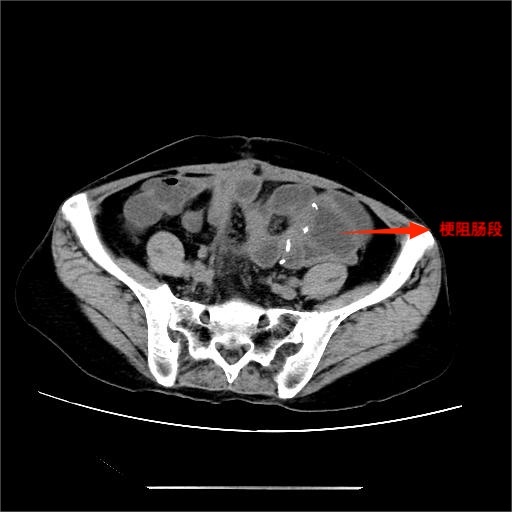

入院后,完善相关检查,腹部立位平片提示肠管扩张,可见多个液气平面,结合病史考虑术后肠梗阻。经综合评估,决定先行保守治疗,在胃肠外科和疝外科刘奇副主任医师团队协作下,为患者置入肠梗阻导管。置管后,患者腹胀、腹痛症状明显缓解,胃肠减压引流通畅,肠鸣音逐渐恢复。经精心护理及营养支持,患者肛门排气排便恢复正常,复查腹部平片示肠管扩张较前明显改善,无液气平面。病情持续好转,顺利出院。

肠梗阻导管由硅橡胶制成,富于柔韧性。经鼻型肠梗阻导管置入术是指在胃镜或X线引导下,应用导丝将经鼻型肠梗阻导管插至空肠近端或以远的深部小肠,进行全程引流和减压的一种非血管介入技术。经鼻型肠梗阻导管全长约3米,经鼻置入后可以随着肠道蠕动到远端小肠,可行全小肠的持续吸引和减压。尤其对于低位小肠梗阻患者,胃管的引流效果非常有限,而肠梗阻导管可以轻松到达梗阻部位上方,有效吸引肠道内容物,充分减轻肠道压力,加快恢复肠道通畅。